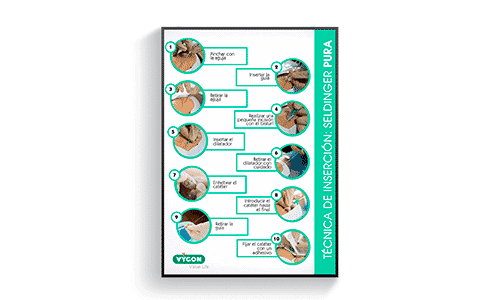

Técnica de inserción Seldinger pura